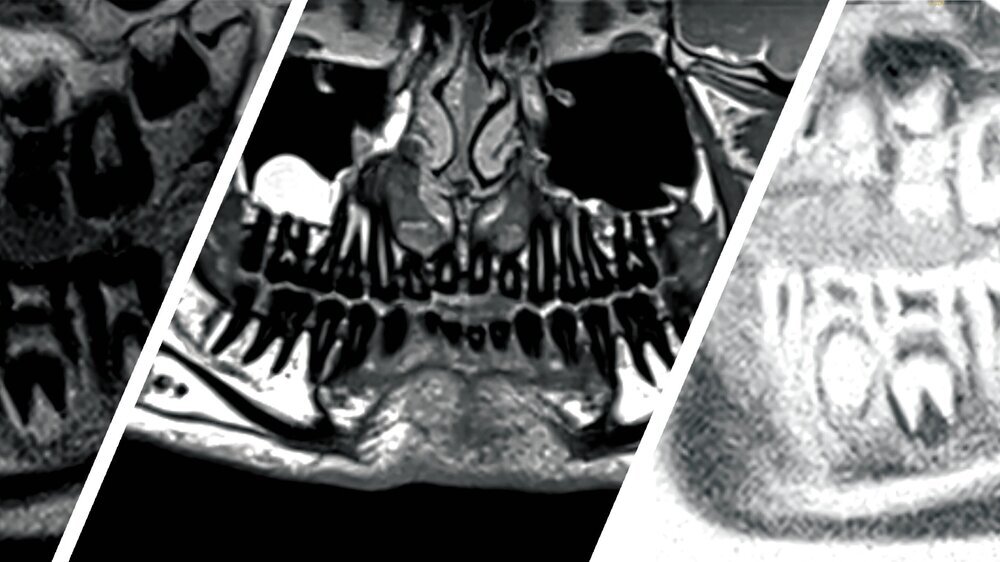

Ein achtjähriger Patient stellte sich mit einer tastbaren Raumforderung regio 36 vestibulär und intermittierenden Schmerzen vor. Während im Röntgen nur unspezifische periapikale Strukturveränderungen zu sehen waren, zeigte das MRT gut sichtbar eine entzündliche Läsion, vereinbar mit einem intraossären Abszess. Differenzialdiagnostisch konnten ein Hämangiom oder ein Tumor ausgeschlossen werden. Postoperativ konnten dank der strahlenfreien Bildgebung Verlaufsaufnahmen angefertigt werden – so ließ sich ein Rezidiv ausschließen.

Abb. 1: Panoramaschichtaufnahme mit kaum sichtbarer Läsion mit unspezifischer periapikaler Strukturveränderung an Zahn 36 im altersentsprechenden Wechselgebiss

Abb 2: Koronares MRT-Bild (inflammation_3d) durch die Mitte der Läsion, 1 = Zahn 36, 2 = Läsion: Gut sichtbar ist die Ausdehnung der entzündlichen Läsion von der Unterkieferbasis bis zur Bifurkation des Zahnes 36.

Abb. 3: Verlaufskontrolle mit Panorama-Rekonstruktion acht Wochen postoperativ auf Basis der Anatomie-3D-Sequenz mit 0,5 mm Schichtdicke und 1 mm Abstand zwischen den Schichten, 1 = mesiale Wurzel des Zahnes 36, 2 = restliches Granulationsgewebe nach Abheilung